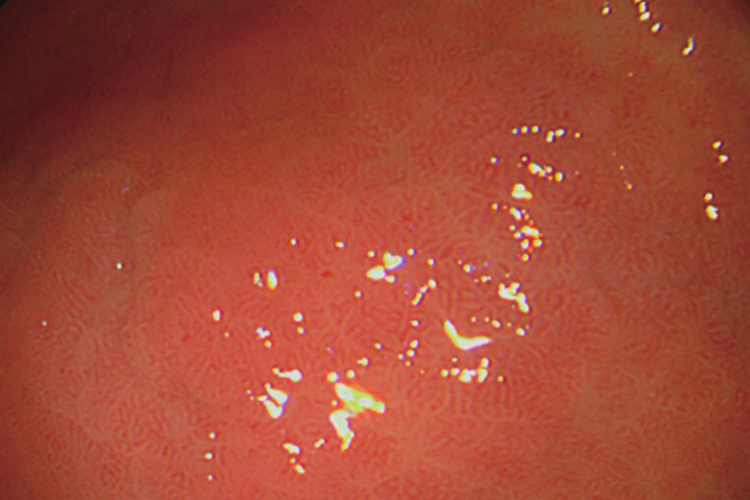

胃黏膜肠化又称胃黏膜肠上皮化生,镜下可观察到有淡黄色结节型、瓷白色小结节型、鱼鳞型、弥漫型四种类型。

瓷白色小结节型:表现为孤立或多发的瓷白色细小结节,呈半透明状,表面光滑、柔软,镜下反光较正常胃黏膜强。